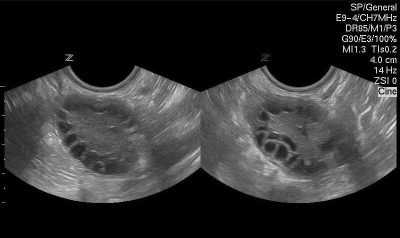

В процессе роста происходит множество клеточных процессов, внутри пузырька-фолликула образуется полость с жидкостью, в которой есть ооцит первого порядка. Такие фолликулы уже можно оценить на УЗИ, они называются антральными. Их размеры уже равны 3-4 миллиметрам.

Как проверить?

Самостоятельно измерить фолликулы, конечно, невозможно. Единственный способ сделать это — посетить врача и сделать фолликулометрию. Это разновидность ультразвукового исследования (УЗИ), при котором в динамике наблюдают состояние яичников женщины. Первое УЗИ обычно делают сразу после окончания менструации, обычно на 7-8 день цикла есть все возможности оценить количество антральных пузырков. Потом УЗИ делают несколько раз с регулярностью через 2-3 суток, чтобы иметь возможность не упустить день овуляции.

Врач УЗИ, основываясь на среднестатистических размерах фолликула, подскажет, когда лучше проводить стимуляцию овуляции, когда лучше назначать процедуру изъятия яйцеклеток методом пункции яичников в протоколе ЭКО, а также с уверенностью сможет сказать, была ли в текущем цикле овуляция вообще.

Фолликулометрия обязательно проводится для установления характера и причин бесплодия, а также для принятия решения о целесообразности стимуляции.

Созревшие ооциты видны невооруженным глазом на экране УЗИ-сканера. В норме за один менструальный цикл созревает от 1 до 3 доминантных фолликулов.

В процессе стимуляции суперовуляции врачами контролируется скорость роста половых клеток, которая осуществляется с помощью трансвагинального УЗИ. Обследование начинают через пять дней после начала гормональной терапии. При недостаточном развитии органических структур яичников увеличивается доза принимаемых лекарств.

Скорость роста женских половых клеток составляет не более 2 мм в сутки. Когда диаметр фолликулов достигает 16 мм, пациентку подготавливают к пункции для забора ооцита. К моменту начала процедуры оценивается состояние эндометрия, толщина которого должна находиться в пределах от 7 до 9 мм.